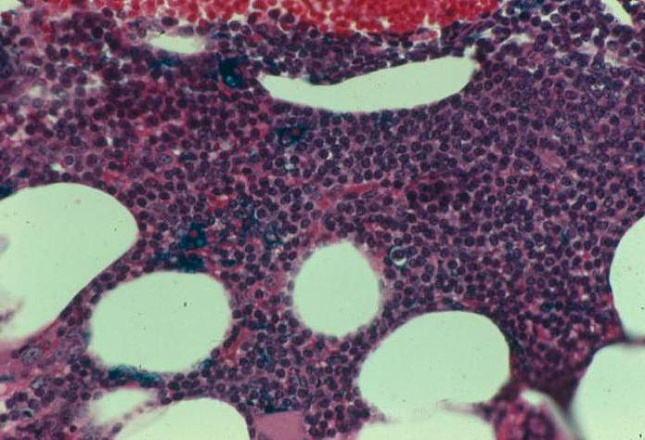

• Гистология костного мозга выявляет гиперпластические процессы, увеличения количества бластных клеток, а биопсия поражённого лимфоузла – аномальное разрастание коллагена и злокачественную гранулёму.